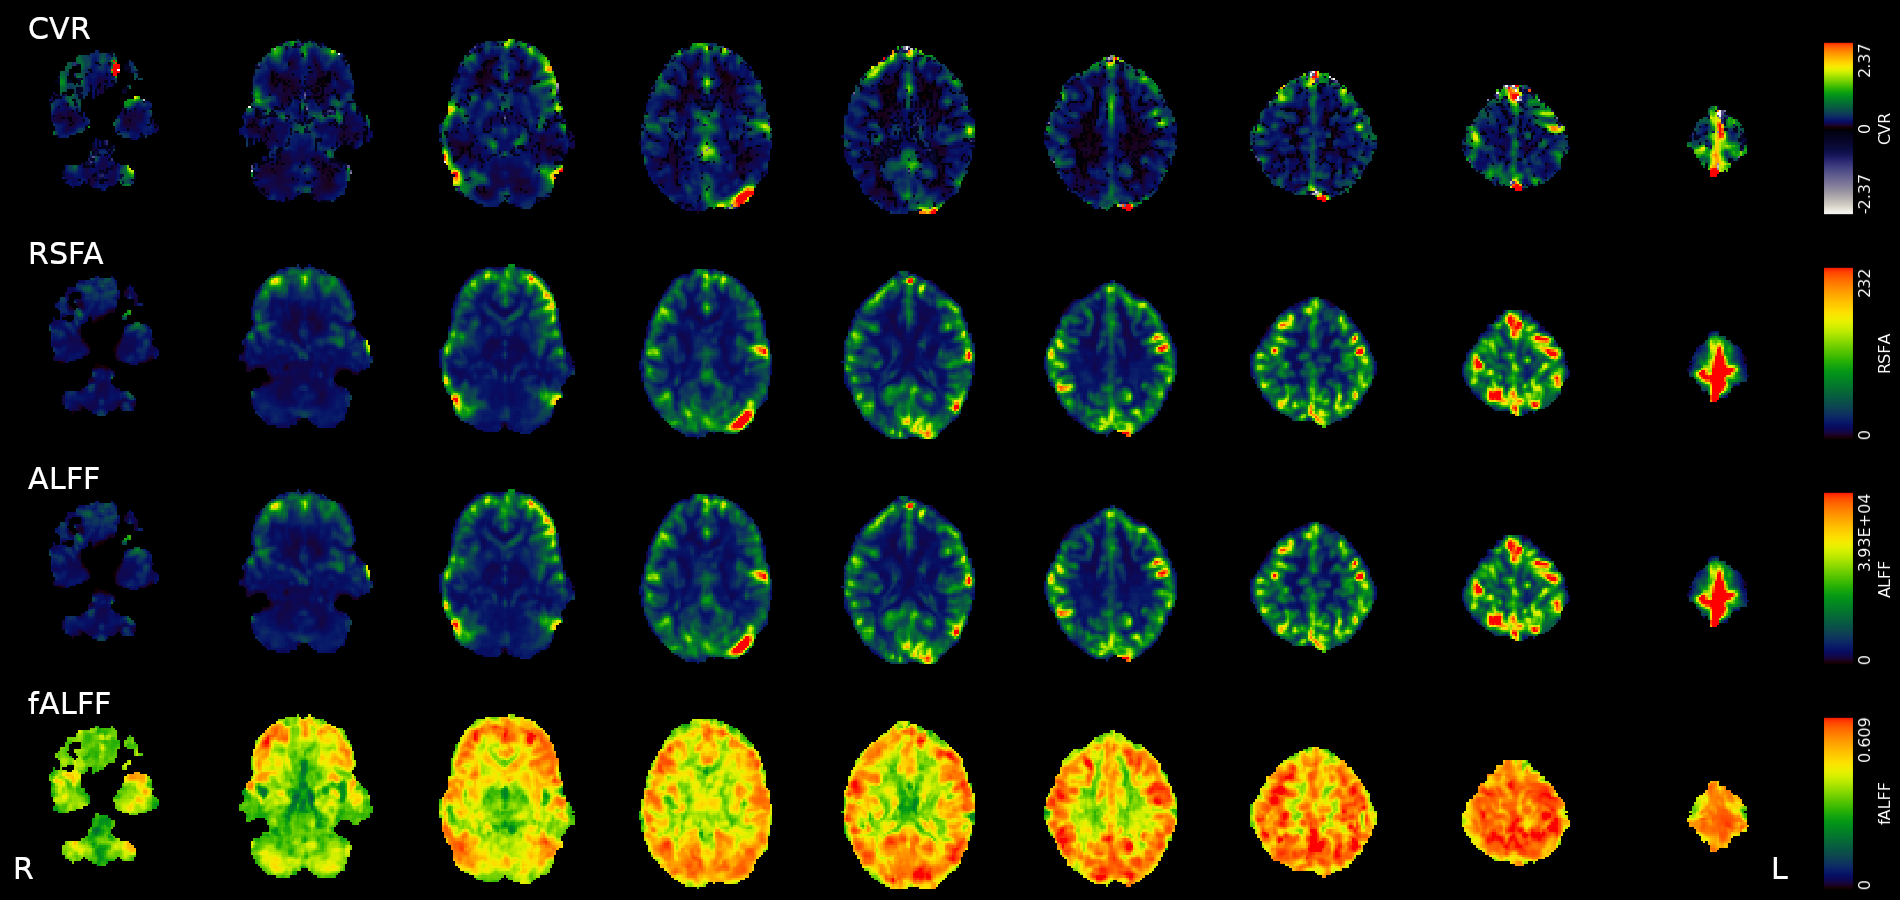

Results: CVR amplitude maps

Moia et al. 2021 (NeuroImage)

An alternative estimation of CVR (?)

2. Golestani et al. 2016 (NeuroImage)

Estimating CVR with a BH task requires compliant subjects and

dedicated equipment, making it harder to adopt in clinical practice

As a cheaper and feasible alternative, previous literature suggests to use

Resting State fluctuations measures (RSF), such as:

- Resting State Fluctuations Amplitude (RSFA)¹

- [fractional] Amplitude of Low Frequency Fluctuations ([f]ALFF)²

1. Kannurpatti et al. 2014 (PloS ONE)

An alternative estimation of CVR (?)

Text

[Zou et al. 2013 (Hum. Brain Mapp.)]

[Kannurpatti et al. 2014 (PLoS ONE)]

[Mennes et al. 2011 (NeuroImage)]

Data

- The first RS of the session

- A motor task

- A Simon task (executive functions)

We preprocessed RS, motor, and Simon data similarly to CVR

We computed:

- RSFA, ALFF, and fALFF from the first RS session

- task Induced Activation (tIA) of Motor task, as each movement vs sham

- tIA of Simon task, considering congruent or incongruent responses

- RSFA, ALFF, and fALFF from the first RS session